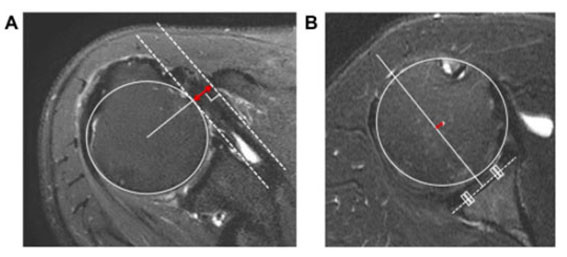

| | ¨Ï ¿Â¾ç½Å¹® | õ¾È¡¤¾Æ»êÃæ¹«º´¿ø Á¤Çü¿Ü°ú À¯À缺 ±³¼ö<»çÁø>°¡ Ã¥ÀÓÀúÀÚ·Î Âü¿©ÇÑ ¾î±ú ȸÀü±Ù°³ ÆÄ¿¿¡ ´ëÇÑ ¿¬±¸ ³í¹®ÀÌ ±¹Á¦ ÇмúÁö¿¡ °ÔÀçµÇ´Â ¼º°ú¸¦ °ÅµÎ¾ú´Ù.

Á¤Çü¿Ü°ú ¼ö¼ú °ü·Ã ±¹Á¦ÇмúÁöÀÎ ¡®Journal of Orthopaedics¡¯¿¡ °ÔÀçµÈ ¡®The anterior translation of the humeral head leads to a decrease in the coracohumeral distance in subscapularis tear¡¯ ³í¹®Àº ¾î±ú ȸÀü±Ù°³ÀÇ °ß°©Ç졂 ÆÄ¿¿¡¼ ÆÄ¿ ÁøÇà¿¡ µû¶ó º¯ÇüÀÌ ÀϾ´Â °ñ¼º ±¸Á¶¹°¿¡ ´ëÇÑ ¿¬±¸ÀÌ´Ù.

| | ¡è¡è ¡ãÀü¹æÀÇ °ß°©Ç졂 ÆÄ¿ÀÌ ÁøÇàµÉ¼ö·Ï »ó¿Ï°ñÀÇ Àü¹æÀ̵¿°ú ¿À±¸µ¹±â »ó¿Ï °Å¸® °¨¼Ò°¡ ¹ß»ý <»çÁøÁ¦°ø=¾Æ»êÃæ¹«º´¿ø> | ¨Ï ¿Â¾ç½Å¹® | |